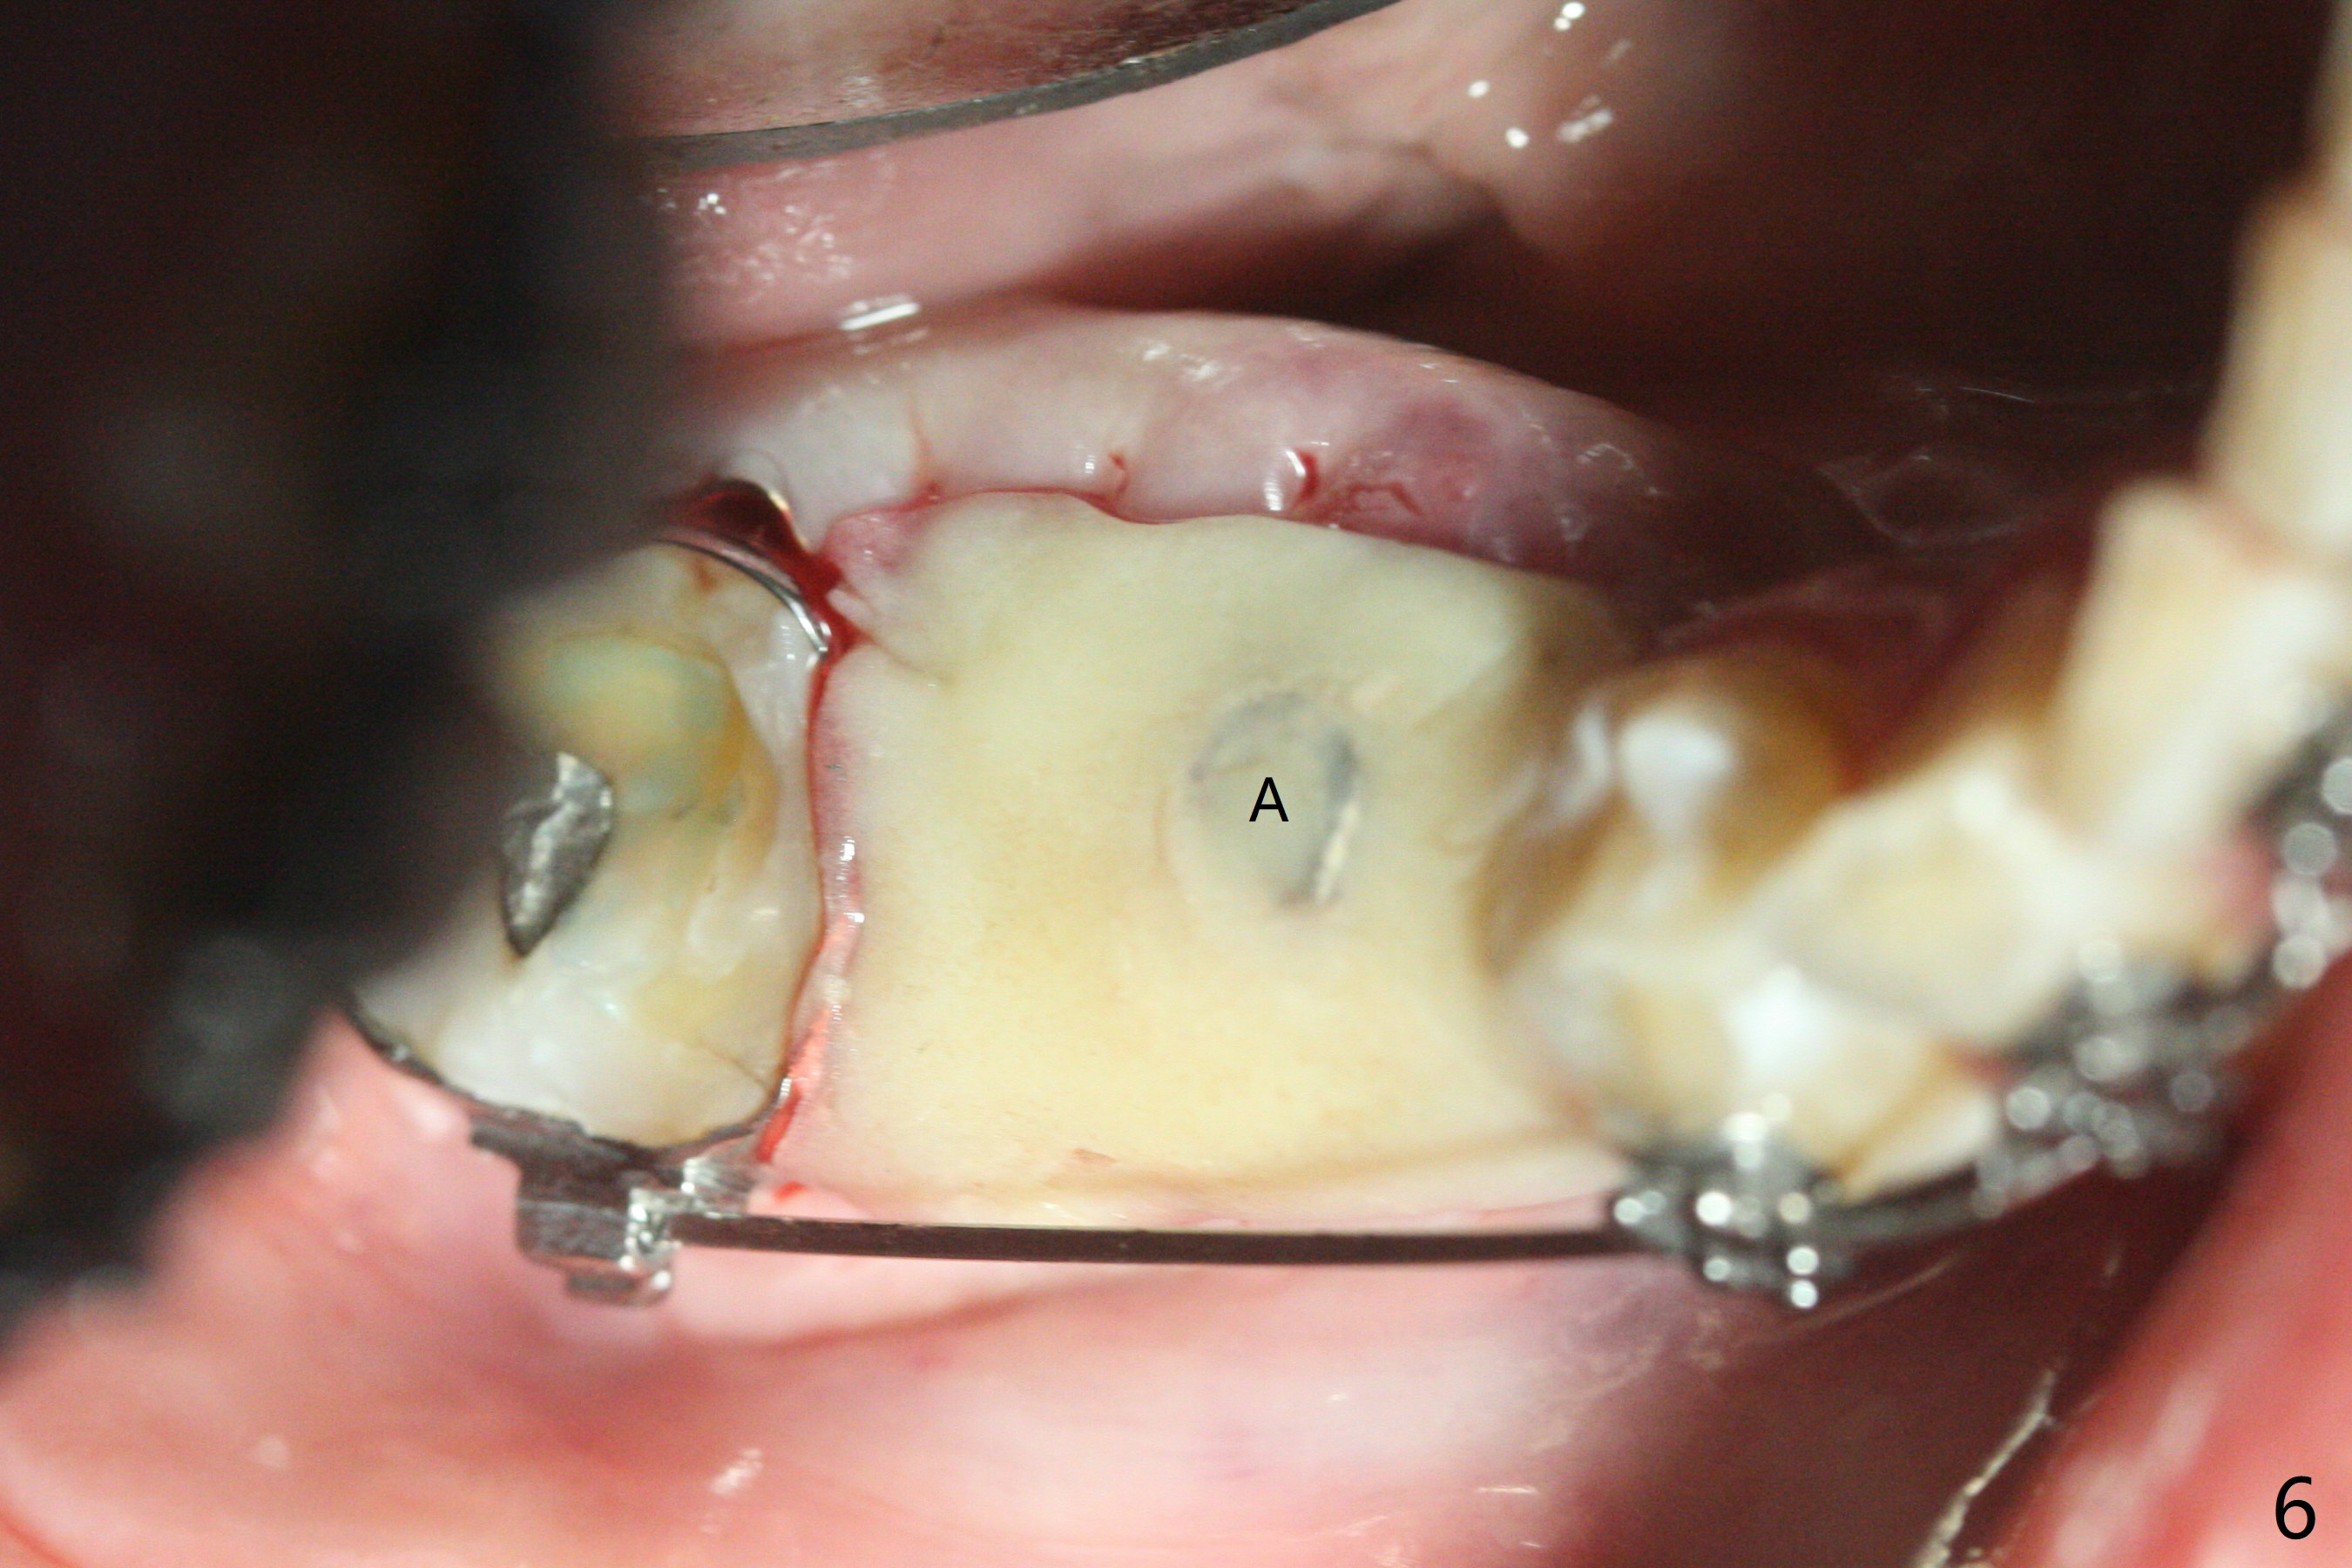

35岁男牙齿矫正后2年5个月右下6远中深龋,拔除后,近中根尖肉芽组织(图零(术前CT冠状切面):*)刮除疼痛,必须阻滞麻醉才能控制疼痛,可能与下牙槽神经分支(图零:红箭头)有关。原先准备在近中牙槽窝近中种植(5x11.5mm),术中发现近中牙槽窝种植好像方便,位置不错,不由自主在那里开始钻洞,由于牙槽窝深,钻洞必须13毫米(图一(接近神经:红虚线)),之后发现钻洞(图二(术前CT3D长轴切面(黑色:近中,远中牙槽窝)):红圆圈)不够理想,使用Lindamann Bur将钻洞往颊侧近中移动(图二:箭头),最终在这方面结果可以(图三,三’,四),虽然接近神经,术后没有神经麻痹。放置粘性骨粉(图四:*),PRF膜,4-0 PGA缝线(图五),最后使用树脂敷料(图六:A)。后牙垂直空间少,术后一周需要降低树脂敷料高度(图七)。术后一个月取出敷料,牙槽窝愈合,植体平台远中稍微暴露(图八),准备一个月后制作临时牙冠。术后两个月植体远中没有暴露,但是基台远中边缘太高了(图九:>),换成6x4毫米愈合基台。下个月换成袖短的修复性基台,安置临时牙冠,牵拉7。舌侧cleats之间放置power chains,颊侧power hooks。其实术后4个月安置临时牙冠和band(图十),牙冠牙合面加高,这样7可以无阻挡移动(图十一:*;16x22 arch wire)。7远中放置power hook行不通,因为末端碰到颊侧前庭牙龈,造成创伤。只好用7颊侧原有牵引勾,在6近中安置一个短的power post (? 图十:箭头),按常规post往下,之间放置12毫米closed spring。如果post往上安置,7牙根牵引可能更有效?近中牵引一个月,第二磨牙前移大约2毫米(图十二:^),稍微近中倾斜,closed spring从12毫米更换到9毫米,舌侧换新的power chains x 4。下一个预约,用sensor 1拍摄根尖片证实第二磨牙近中倾斜,然后在它远中16x22钢丝安放power hook,下缘向颊侧弯曲,避免接触接触粘膜。